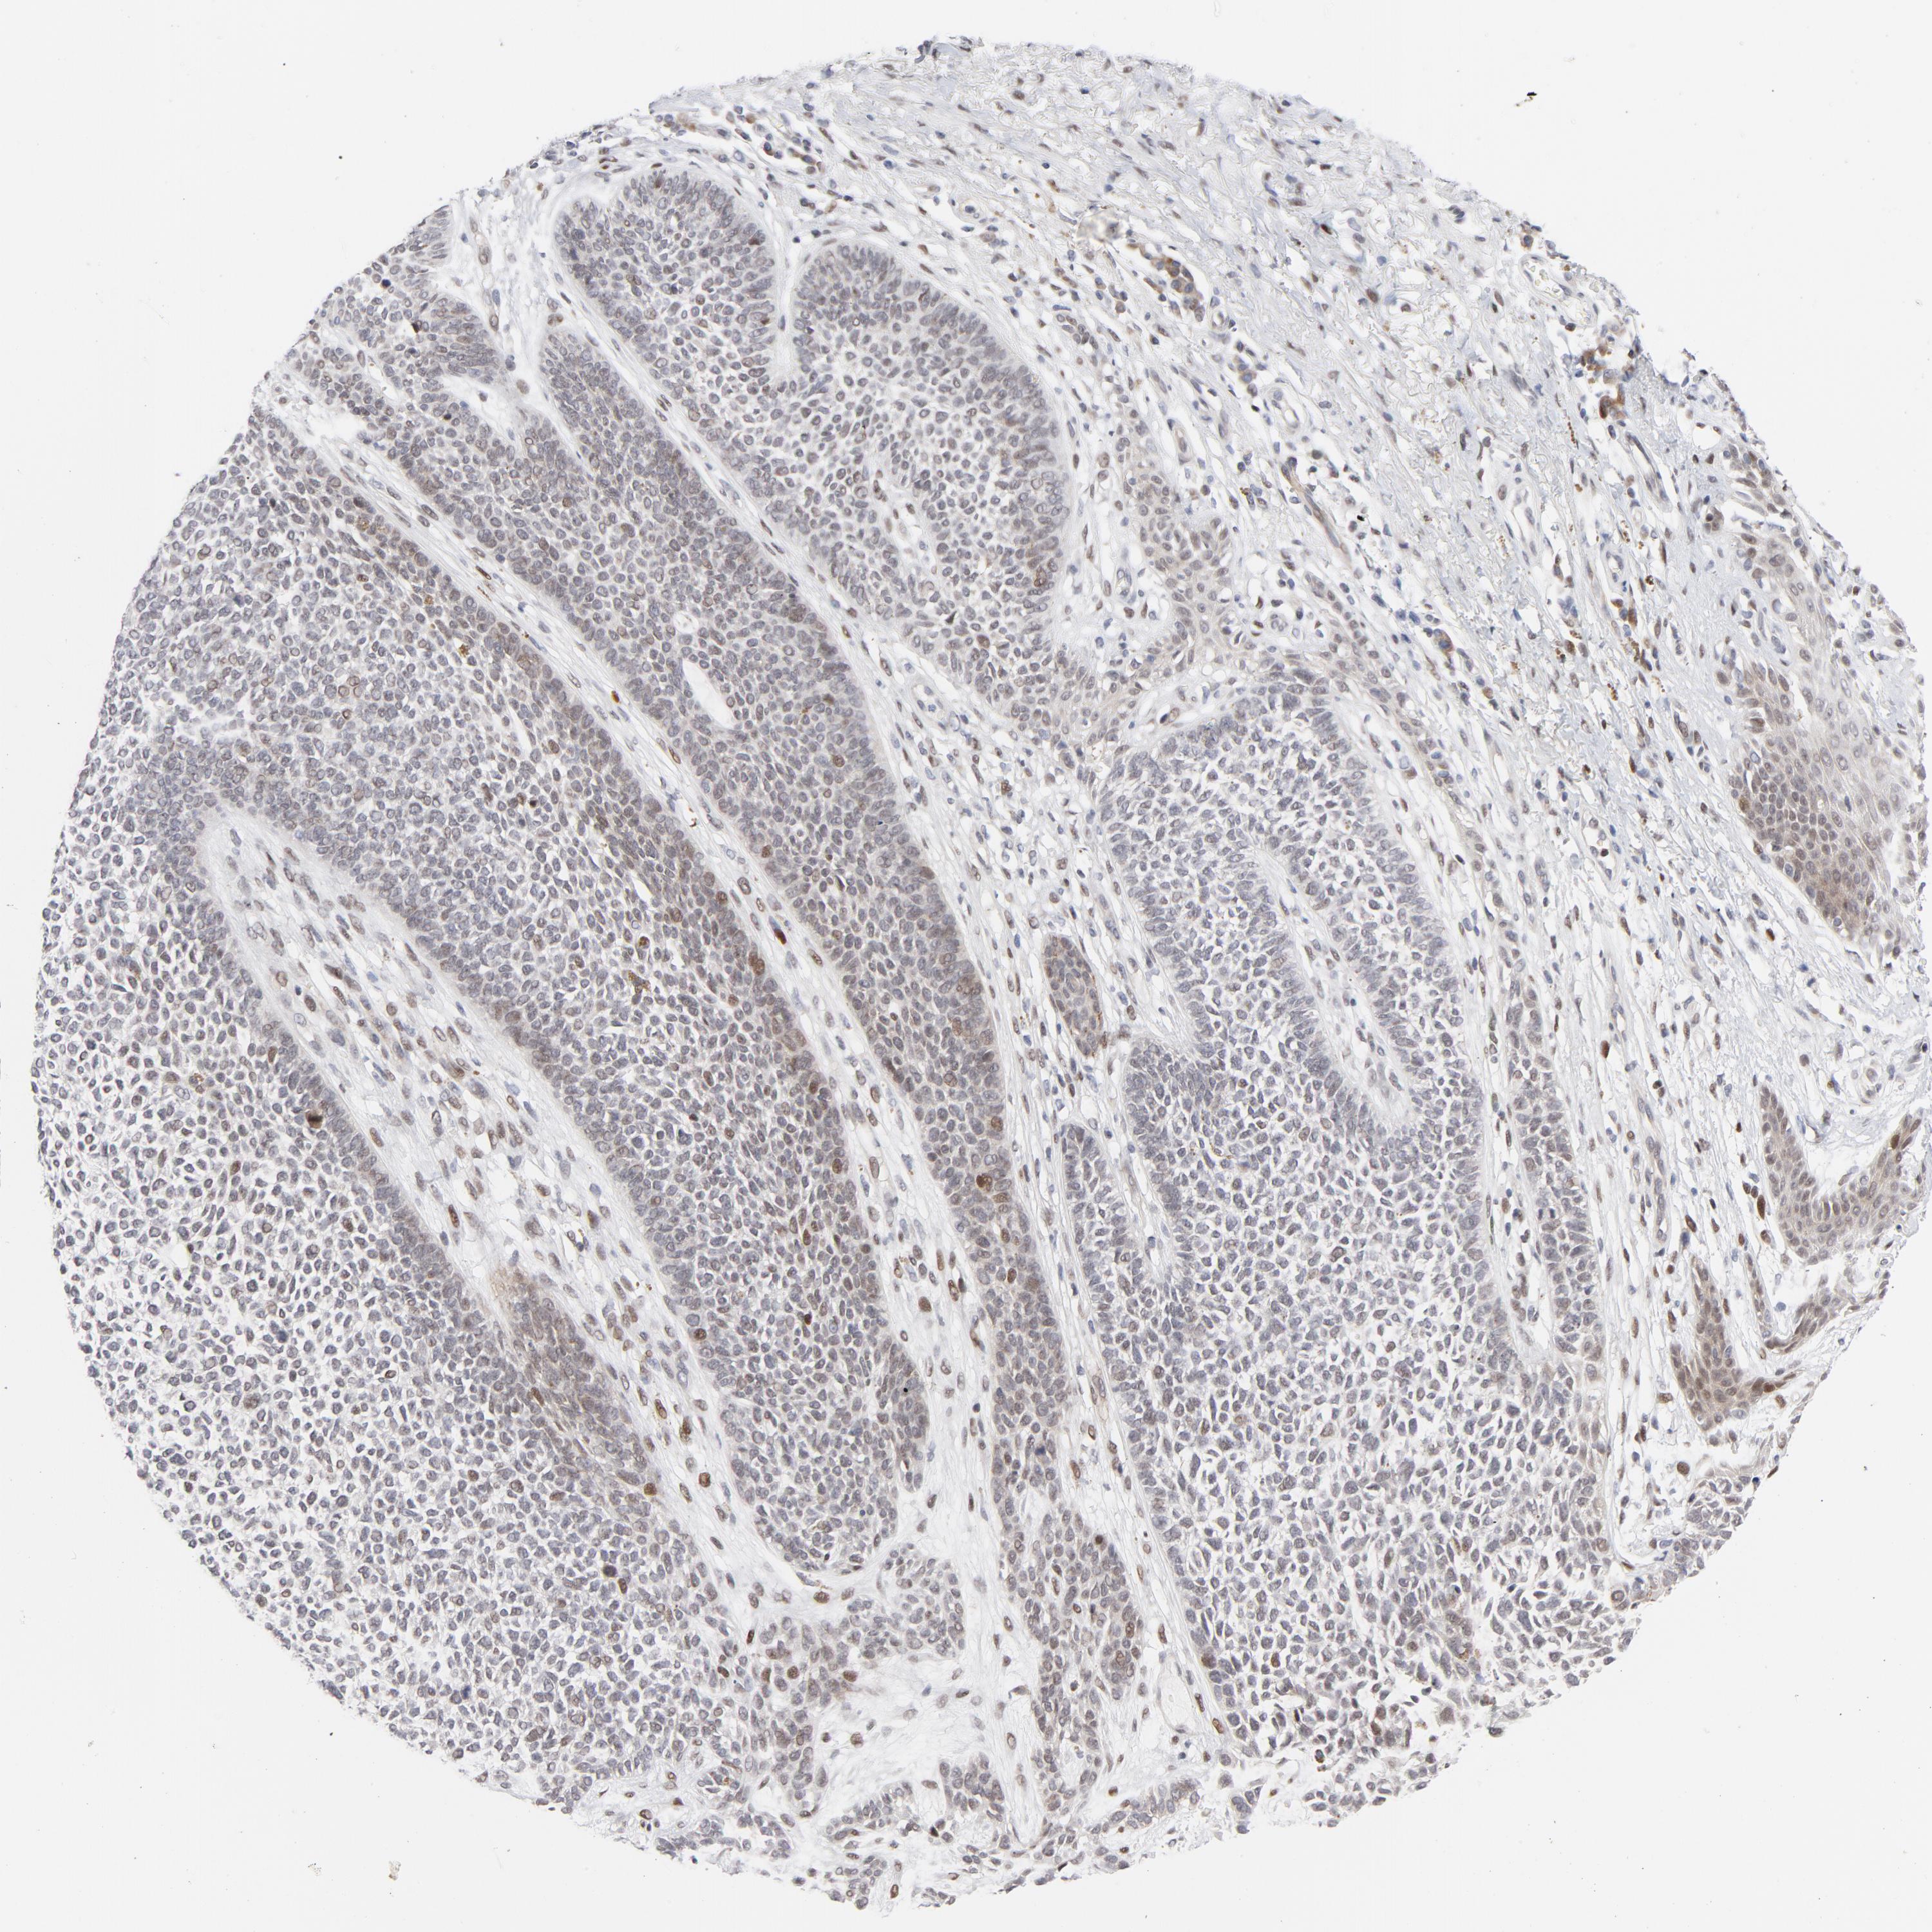

SKIN CANCER - Protein expressioni

A mouse-over function shows sample information and annotation data. Click on an image to view it in a full screen mode. Samples can be filtered based on level of antibody staining by selecting one or several of the following categories: high, medium, low and not detected. The assay and annotation is described here.

Antibody stainingi

Antibody staining in the annotated cell types in the current human tissue is reported as not detected, low, medium, or high, based on conventional immunohistochemistry profiling in selected tissues. This score is based on the combination of the staining intensity and fraction of stained cells.

Each image is clickable and will lead to virtual microscopy that enables deeper exploration of all samples and also displays staining intensity scores, fraction scores and subcellular localization as well as patient and tissue information for each sample.

Antibody CAB004674

Staining

High

Medium

Low

Not detected

Intensity

Strong

Moderate

Weak

Negative

Quantity

>75%

75%-25%

<25%

None

Location

Nuclear

Cytoplasmic/membranous

Cytoplasmic/membranous,nuclear

Basal cell carcinoma

Squamous cell carcinoma, NOS